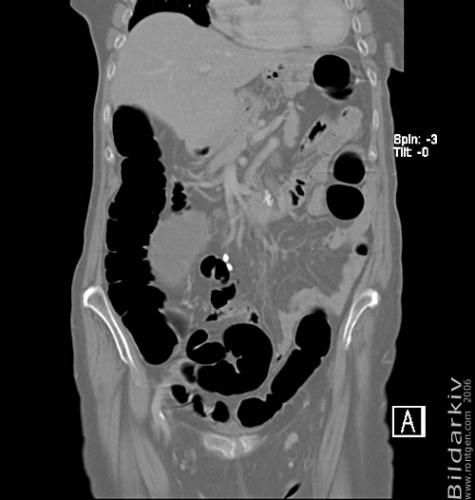

CT colon 21

Datortomografi av tjocktarmen (colon) med infunderad luft i tarmen samt med kontrast i blodbanan. Koronar bildserie.

CT multislice 16